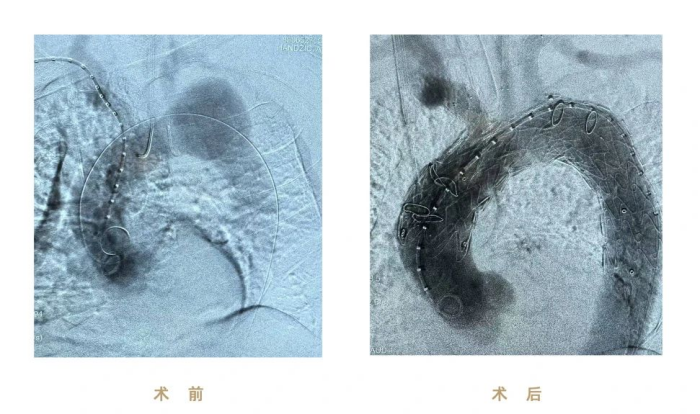

本例手术患者罹患复杂主动脉弓动脉瘤,累及左锁骨下动脉及降主动脉,并伴明显血管弯曲与结构异常,术中面临多项高难度挑战:

① 弯曲解剖结构导致支架定位偏差风险高,极易影响分支对位与瘤体隔绝效果

② 左锁骨下动脉因受瘤体挤压呈弯折状态,分支支架植入时导丝通过、支架输送困难

③ 主动脉弓毗邻心脏、气管等重要器官,操作空间狭窄,术中容错率极低

(图:术前、术后影像)

本次手术使用九州ku酷游CS一体式弓部三分支重建系统进行腔内修复,逐次完成通路建立、CS主体支架植入及精准释放、弓上三分支(无名动脉、左颈总动脉、左锁骨下动脉)依次超选及分支支架植入,全程造影显示支架形态良好、无移位及内漏、三分支血流通畅,达到理想的隔绝与血供重建效果。